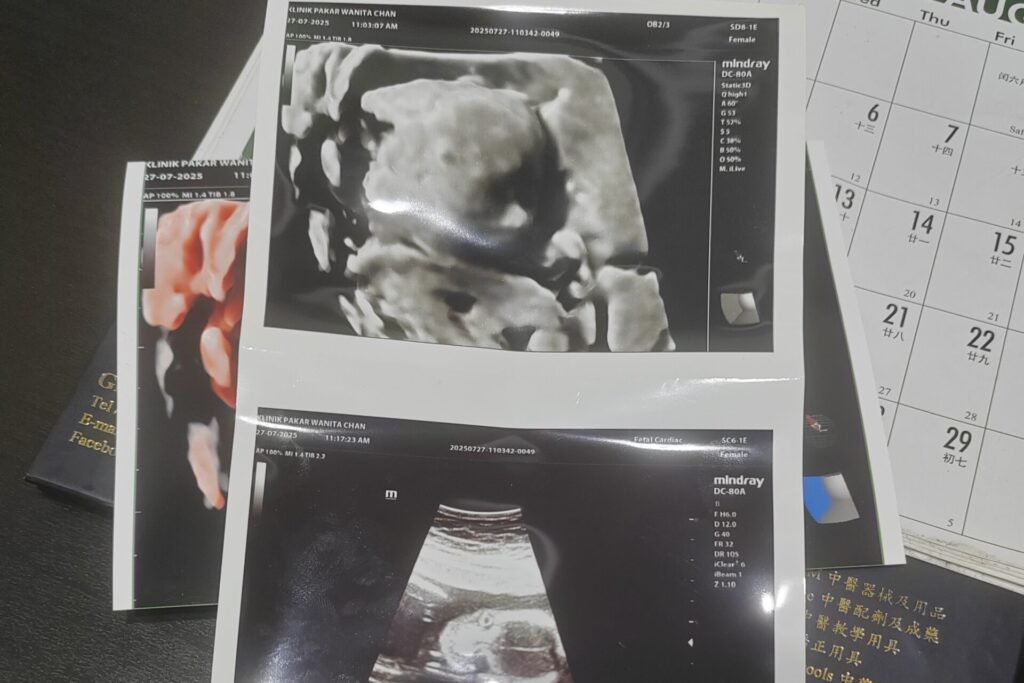

Real Success Story: From Recurrent Miscarriages to Natural Pregnancy (Ms C, 28)

Ms C, 28, had experienced three miscarriages due to Protein S Deficiency, including an empty sac (W5) in July 2024 and a biochemical pregnancy in November 2024.

After just one month of personalised TCM regulation, she conceived naturally.

Throughout early pregnancy, she continued combined care with both Western medicine and TCM.

Outcome:

Her pregnancy progressed normally with stable development—showing how targeted TCM support can help women with recurrent miscarriage regain balance and improve natural pregnancy success.